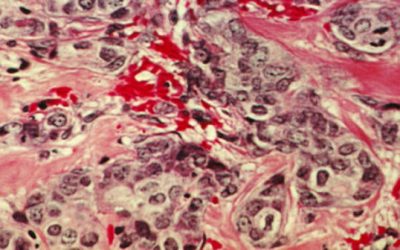

What Is Metastatic Breast Cancer? Doctors Explain the Advanced Form of the Disease

Up to 30% of patients with early-stage breast cancer will go on to develop a metastatic form of the disease—here's what to know. Breast cancer is one of the most common cancers in the world, making up an estimated 11.7% percent of new diagnosed cancer cases...

Breast cancer stem cells may use an arteriolar niche to prepare for metastasis

Most breast cancer deaths will occur after the cancer has spread to other organs. Metastasis involves at least five major steps. Two early steps are invasion of the basement membrane and cell migration, and then a movement of the cancer cell through the wall and...